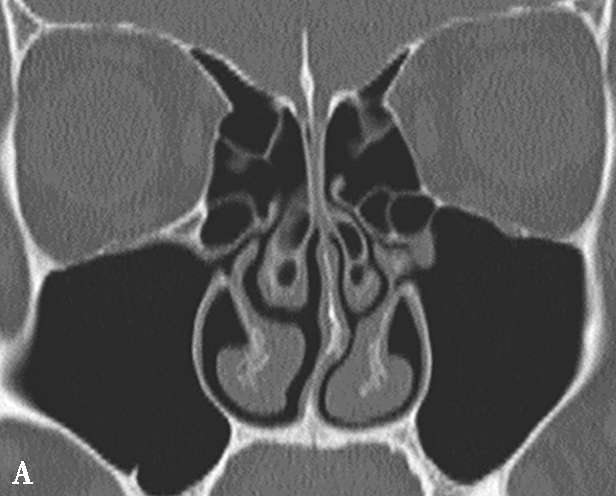

鼻丘气房位于筛漏斗的前上部,与泪骨、上颌骨、筛骨、额骨、鼻骨关系密切。是由筛漏斗直接发展而来。鼻丘气房通常位于额窦底的前部,构成额隐窝的前壁,大小不一,过大、过多可妨碍额窦引流,引起额窦炎。鼻丘气房和钩突眶内壁附着点之间的关系非常密切。当钩突与眶内壁没有附着点时,鼻丘气房不存在;当钩突与眶内壁仅有一个附着点时,鼻丘气房存在;当钩突与眶内壁有两个及以上附着点时,形成上下两个气房,在冠状面观察,偏下的气房称为鼻丘气房,偏上的气房称为额气房,两者内壁均由钩突构成(图1-3-1)。

图1-3-1 鼻丘气房及额气房CT解剖

A~C.鼻丘气房(五角星),额气房(星),钩突(白箭),筛骨纸板(箭头)